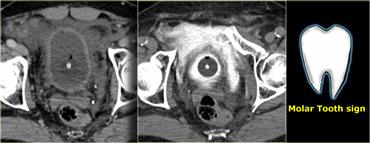

Bên trái là hình ảnh trước và sau khi chụp CT bàng quang cản quang.

Có thuốc cản quang trong lòng bàng quang bao quanh ống thông Foley và có hiện tượng thoát thuốc cản quang vào khoang trước bàng quang hay khoang Retzius.

Hình ảnh này được gọi là ‘dấu hiệu răng hàm’ (molar tooth sign), gợi ý vỡ bàng quang ngoài phúc mạc.

Bên trái là tái tạo mặt phẳng đứng dọc và đứng ngang.

Lưu ý không có thuốc cản quang lan vào rãnh cạnh đại tràng, do đó không có sự lan rộng vào trong phúc mạc.